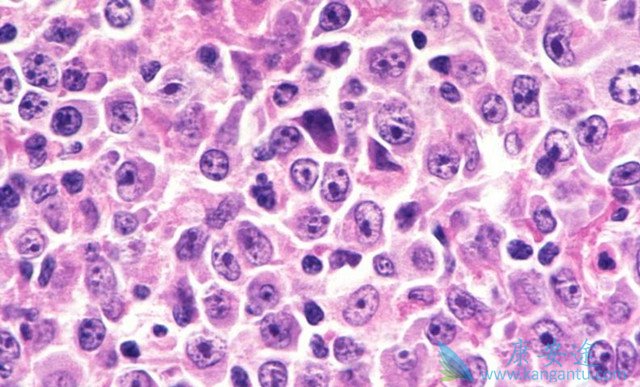

弥漫性大B细胞淋巴瘤是目前最常见的成人非霍奇金恶性淋巴瘤,占西方国家成人非霍奇金恶性淋巴瘤的30~40%,在发展中国家,所占的比例更高,达60%。在儿童淋巴瘤中,DLBCL所占的比例在10%以下。DLBCL发病年龄范围很广,平均发病年龄70岁,但亦可见于儿童;男性患者多于女性。WHO对弥漫性大B细胞淋巴瘤的定义是大的肿瘤性B淋巴细胞呈弥漫性生长,肿瘤细胞的核与正常组织细胞的核相近或大于组织细胞的核,细胞大小不小于正常淋巴细胞的两倍。

肿瘤细胞为大的转化淋巴细胞,体积在不同的病例或同一病例中可有很大不同,核大于反应性组织细胞的核。但在一些病例中,核中等大小,造成与Burkitt(伯基特)样淋巴瘤鉴别困难。核呈圆形、锯齿状或不规则折叠,染色质空泡状或粗颗粒状,常有核仁,大小不等、嗜碱或嗜酸性、一个或多个。胞浆中等量或丰富,可透明、淡染或嗜双色。一些病例中的瘤细胞呈浆细胞样:嗜碱性、嗜派洛宁,伴有淡染的核周高尔基空晕。可有嗜碱性胞浆碎片,与炎症反应中的“浆细胞小体”不易区分。可见类似于R-S细胞的多叶核细胞或奇异细胞。核分裂像易见。从细胞学的角度,肿瘤细胞形态多样,可进一步进行形态学分类,但各亚型之间免疫表型以及基因学特征无明显差异。因此诊断时既可使用统一的弥漫性大B细胞淋巴瘤亦可采用形态学分类命名。